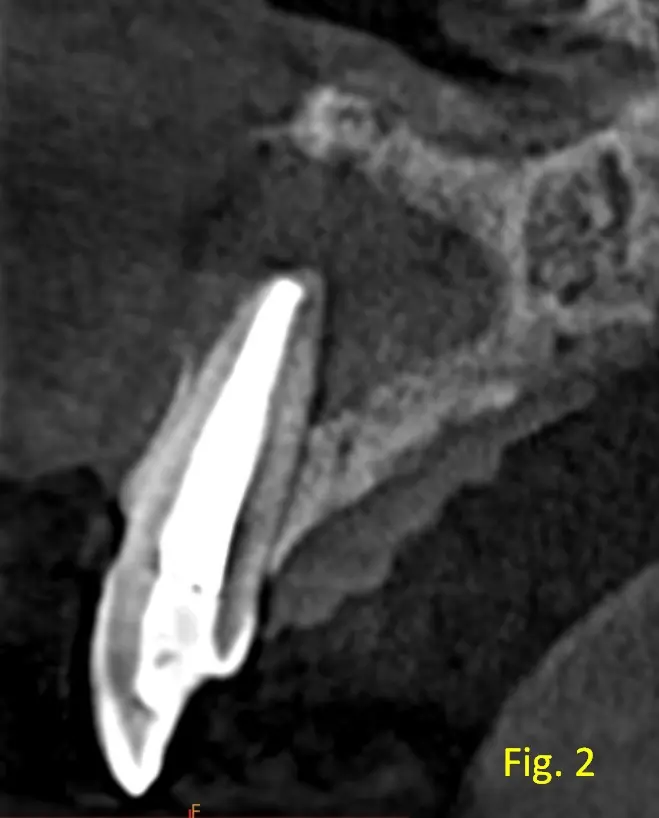

Su contenido es homogéneo, sin tabiques ni calcificaciones. No se observa invasión del piso de fosas nasales ni desplazamiento significativo de raíces vecinas. En el corte transaxial, fig. 2 se confirma la ubicación periapical exacta de la lesión, asociada a la pieza 22 donde se evidencia que la lesión es unilocular y no atraviesa estructuras anatómicas mayores. En la fig. 3, vista axial se observa la ausencia de la tabla ósea vestibular.